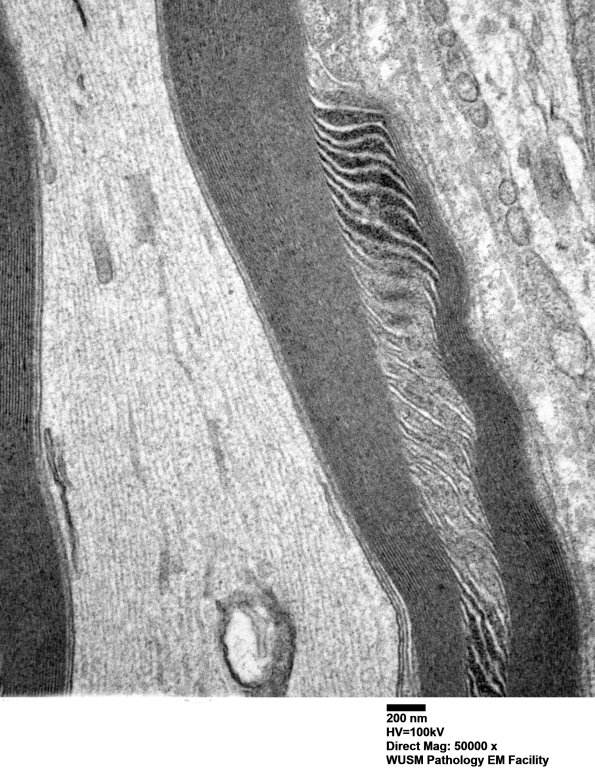

Washington University Experience | PERIPHERAL NEUROPATHY | 3 NORMAL MYELIN & SCHWANN CELLS | 3 Schmidt-Lanterman Clefts | 2A4 W24-3671 Anders G (Case 2) Sural_060 - Copy

Higher magnification of image #2A3. (electron micrograph)